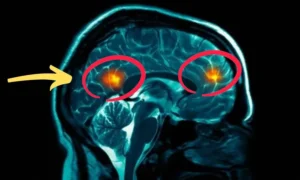

My wife refused to accept it. She found research showing every diabetic amputation starts with “microvascular starvation” — tiny blood vessels collapsing, cutting off oxygen to nerve endings. Without blood flow, nerves can’t repair. They die. By day 6, the ulcer showed pink tissue growth. On June 11th — one day before my amputation — my surgeon said: “We’re canceling the surgery. This is healing.”

She found a naturopath named Barbara O’Neill who discovered a method to reopen collapsed capillaries and restore blood flow to dying nerves. I had 11 days. I had nothing to lose.